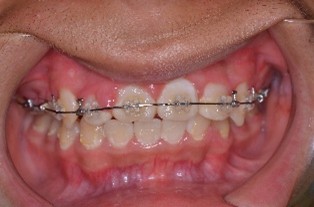

(初診時) (ワイヤー除去前) (ワイヤー除去後)

※この方はワイヤー矯正後、マウスピース矯正に移行しています

(↑ワイヤー矯正後)

ワイヤー矯正は、歯にブラケットとワイヤーをつけていきます。その後1~2か月毎に歯科医院にきてクリーニングや虫歯の有無、歯並びの状態などを確認と調整をしていきます。ある程度並んだ後、ブラケットとワイヤーを外してマウスピース矯正に移行しました。